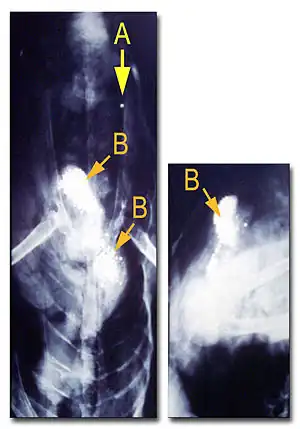

- Le diagnostic est confirmé chez un oiseau mort si son foie contient 6-8 ppm ou plus de plomb (poids humide) et/ou que de la grenaille de plomb est trouvée dans le gésier (l'observation aux rayons X est alors préférable pour distinguer le plomb des graviers). L'absence de billes de plomb dans le gésier ne signifie pas qu'un oiseau n'est pas mort de saturnisme, car les billes de plomb se dissolvent totalement après quelques dizaines d'heures[56] ;